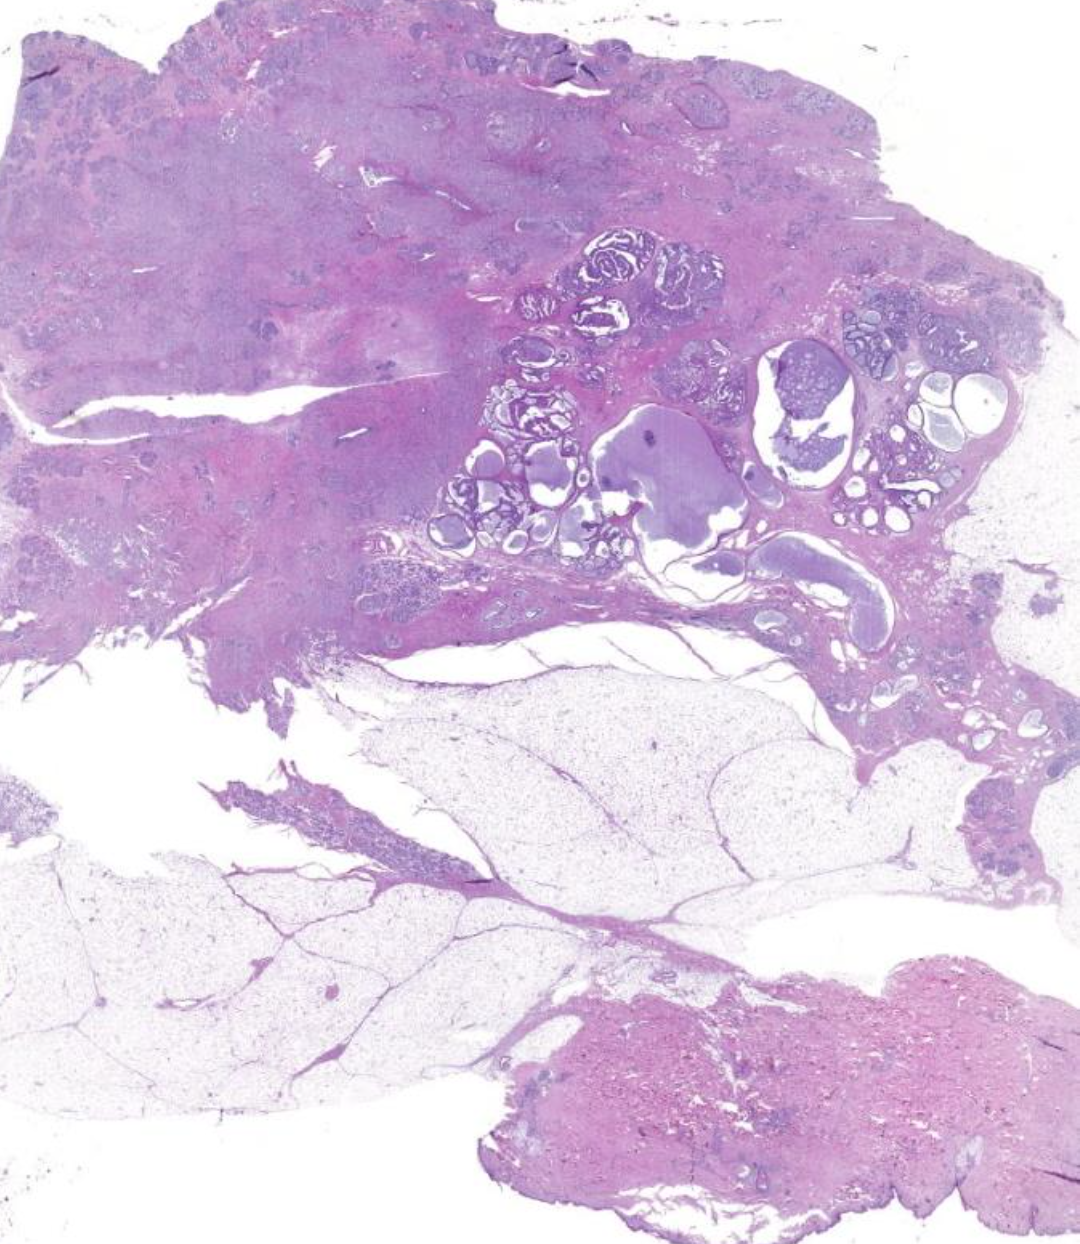

Diagnose?

Pleomorphes Speicheldrüsenadenom = BENIGNE

80% in der Parotis -> nicht destruktiv, nicht invasiv, nur verdrängend

v.a .Parotis, benigne, aufgebaut aus bindegewebiger Kapsel und epithelialen und mesenchymalen Gewebe (v.a. Knorpelgewebe)